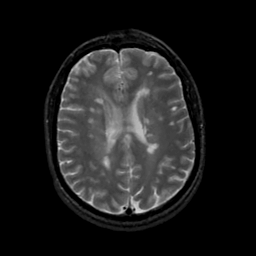

MR Study #19, August 25, 1991 -- Slice #32